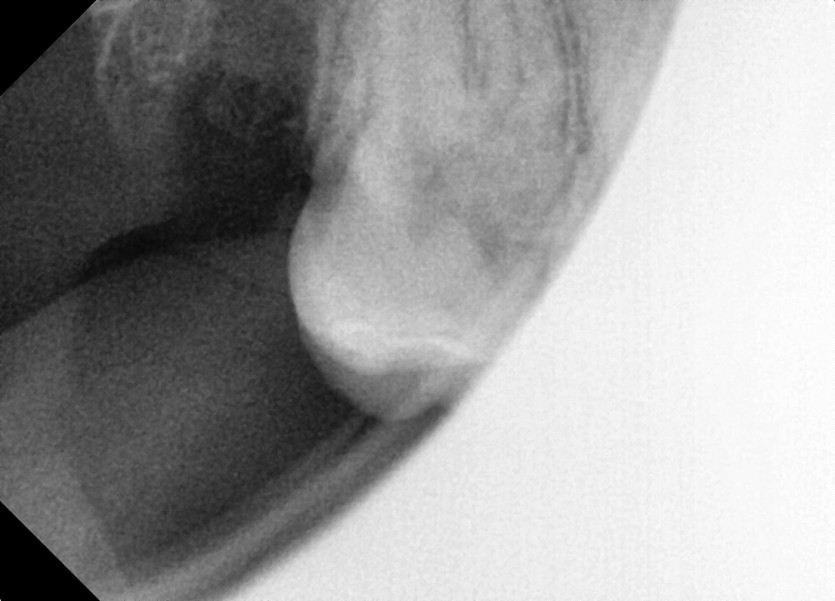

#18,48 사랑니 발치

구강 외과 전문의가 당일 발치했습니다.